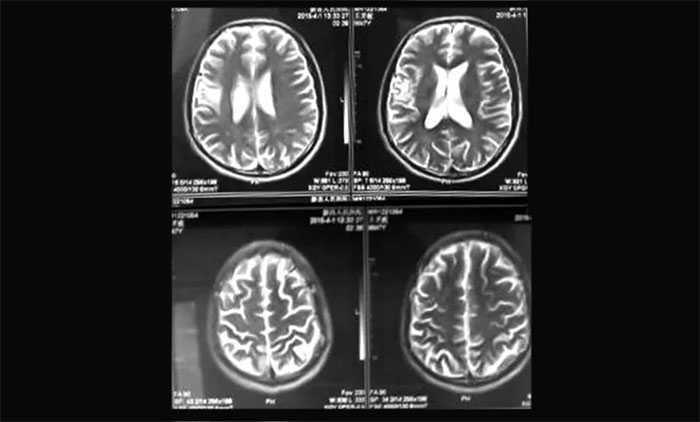

▲ 復(fù)查病灶畸形血管巢已基本消失

通過(guò)完善相關(guān)檢查并征得患者家屬同意后,陳琦主任團(tuán)隊(duì)為胡某開(kāi)展了頭部伽瑪?shù)吨委,過(guò)程順利。后期通過(guò)復(fù)查評(píng)估,患者畸形血管巢已基本閉塞,未出血,頭痛等臨床癥狀得到明顯緩解。